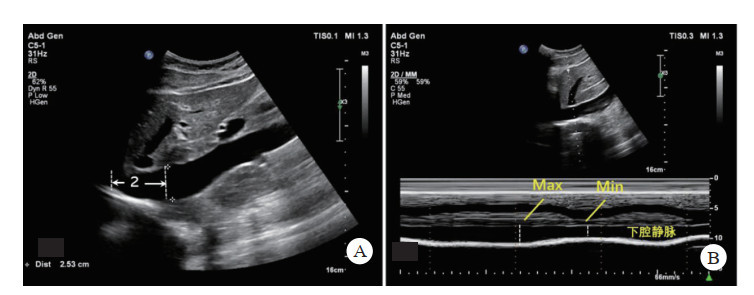

下腔静脉检查常用IVC塌陷率,也称下腔静脉呼吸变异指数(shape change index, SCI),是反映右心房压力的敏感指标。当血容量不足时,IVC塌陷明显增加,当血容量过高时,IVC塌陷率明显减少[46]。

检查方法:采用平卧位,超声切面为剑突下切面,显示下腔静脉汇入右房、肝静脉汇入下腔静脉,M模式下采样线置于离右心房-下腔静脉交接点约2 cm处,测量最大和最小内径,计算出SCI(图 11)。检查时间一般不超过2 min。

| A:正常下腔静脉在剑突下切面右心房交汇处下2 cm;B:下腔静脉M型超声测量最大最小内径 图 11 下腔静脉的测量方法 |